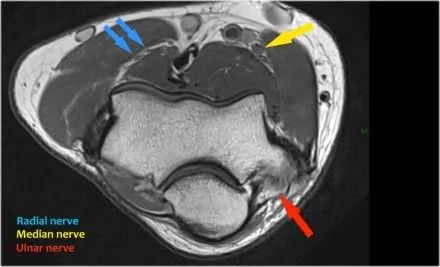

桡神经:在桡骨头水平可以最好地识别桡神经,在那里你可以看到桡骨隧道中的浅表和深支(箭头)。这是寻找桡神经的非常一致的地方。